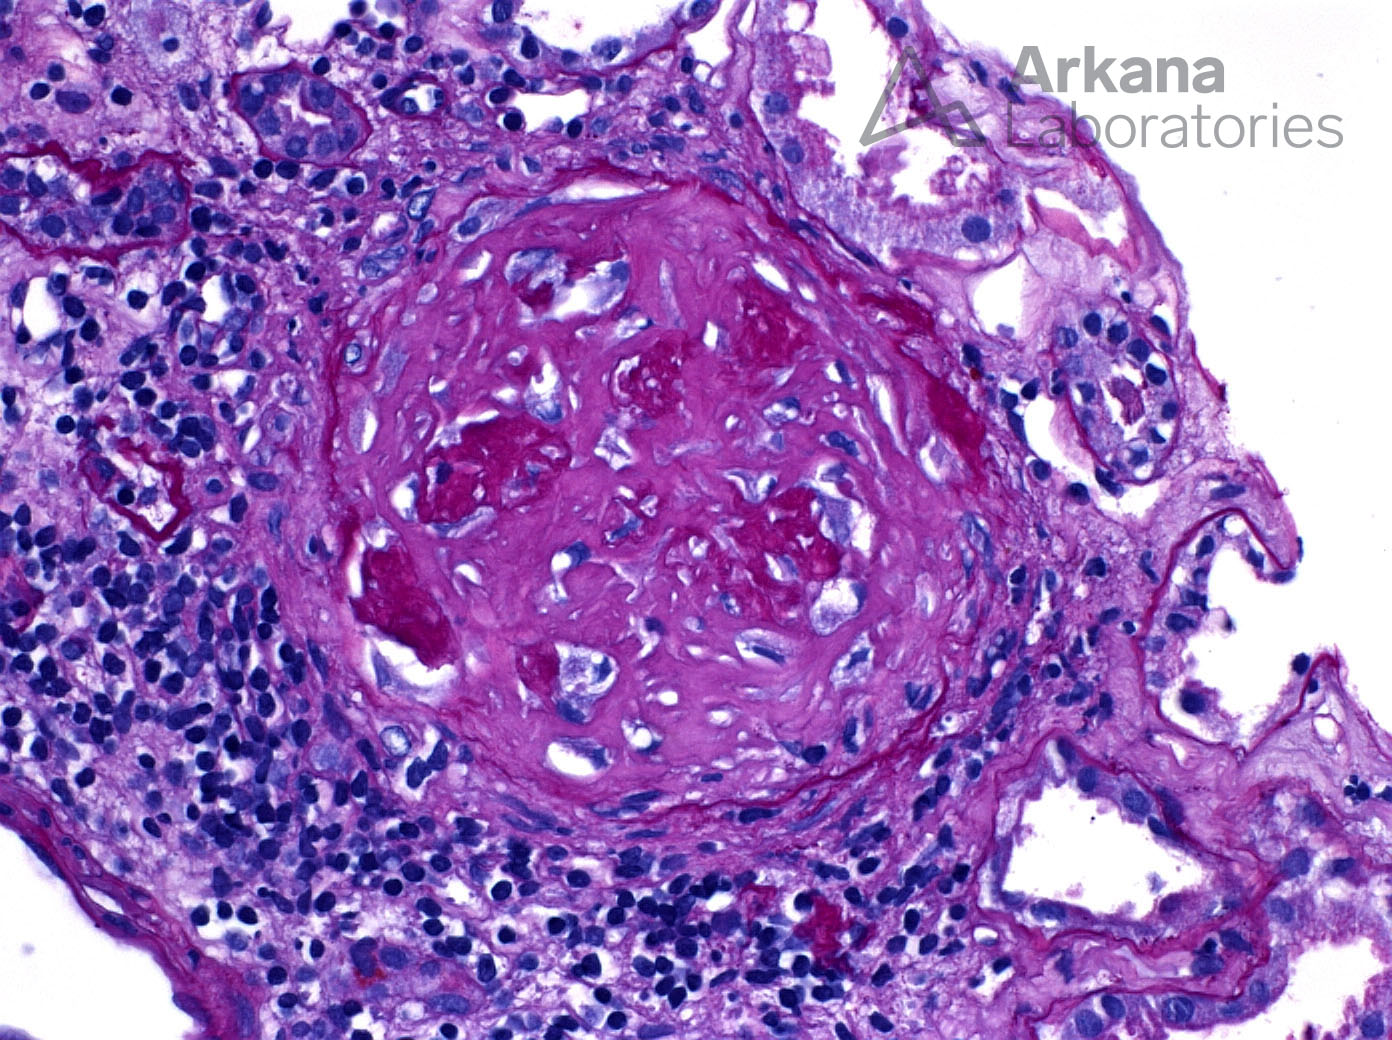

Fibrous Crescent_2